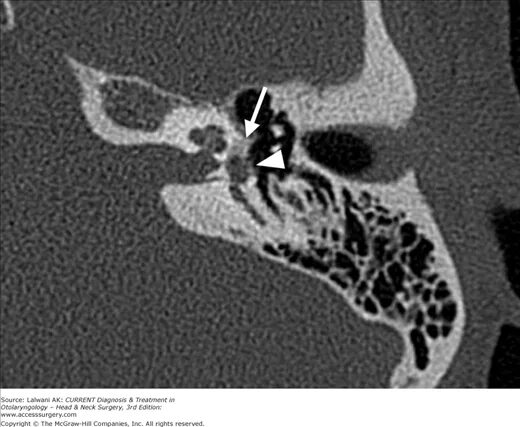

Кохлеарный отосклероз